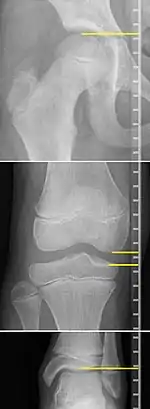

On X-rays, there is generally measurement of both the femur and the tibia, as well as both combined.[4] Various measuring points for these have been suggested, but a functional method is to measure the distances between joint surfaces:[4]

- Femur length: The superior aspect of the femoral head and the distal portion of the medial femoral condyle.

- Tibial length: The medial tibial plateau and the tibial plafond

Clinical measurement of leg length conventionally uses the distance from the anterior superior iliac spine to the medial malleolus.[9] Projectional radiographic measurements of leg length have two main variants:[10]

- Teleroentgenogram, which projects the entirety of both legs at the same time.

- Orthoroentgenogram, which takes separate images of the hip, knee and ankle.

On X-rays, the length of the lower limb can be measured from the proximal end of femoral head to the center of the plafond of the distal tibia.[11]